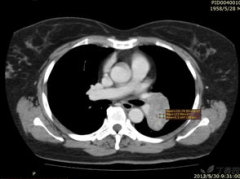

什么是肺占位性的病变,影像学诊断与治疗概览

你知道吗?最近我在网上看到了一个挺有意思的话题——肺占位性的病变。听起来是不是有点吓人?别担心,今天我就来给你详细说说这个神秘的肺占位性病变,让你对它有个全面的认识。什么是肺占位性的病变?想象你的肺部就像是一片宁静的湖面,突然间,湖面上冒出了一个孤岛。这个孤岛,就是肺占位性病变。它可以是良性肿瘤,也...